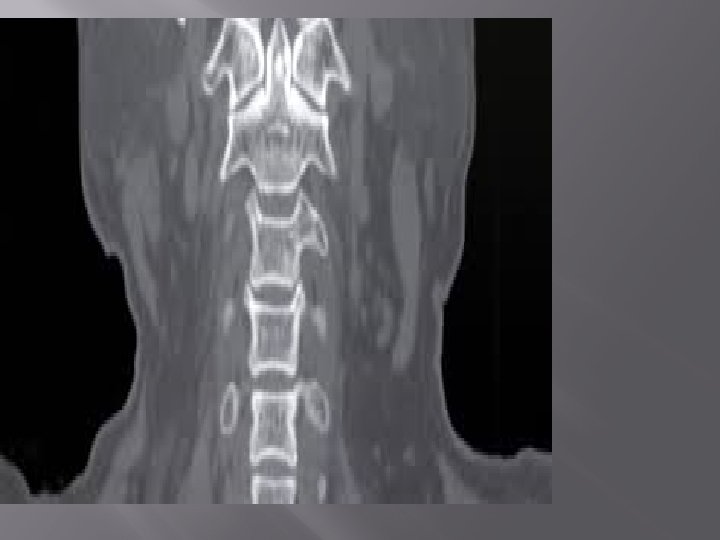

USE FOR… � � � � Diagnose muscle and bone disorders, such as bone

USE FOR… � � � � Diagnose muscle and bone disorders, such as bone tumors and fractures Pinpoint the location of a tumor, infection or blood clot Guide procedures such as surgery, biopsy and radiation therapy Detect and monitor diseases and conditions such as cancer, heart disease, lung nodules and liver masses Monitor the effectiveness of certain treatments, such as cancer treatment Detect internal injuries and internal bleeding Quick and pain less